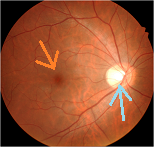

写真だと水色の部分が視神経乳頭(マ盲点)になります。ちなみに、物を見る中心部の網膜は黄斑と呼ばれ、オレンジの矢印に当たります。